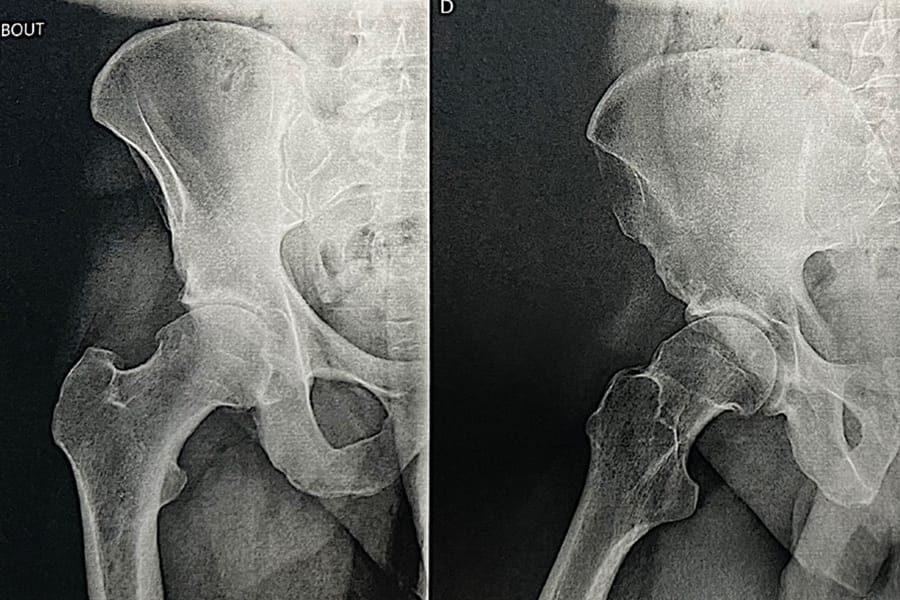

Mise au point Place de la chirurgie prothétique dans le conflit fémoro-acétabulaire ? , Jean-Marie Philippeau Santé atlantique, Avenue Claude Bernard, 44800 Saint-Herblain, France 🖂 jmphilippeau@hotmail.com N°333 - Avril 2024 ● 19 min de lecture